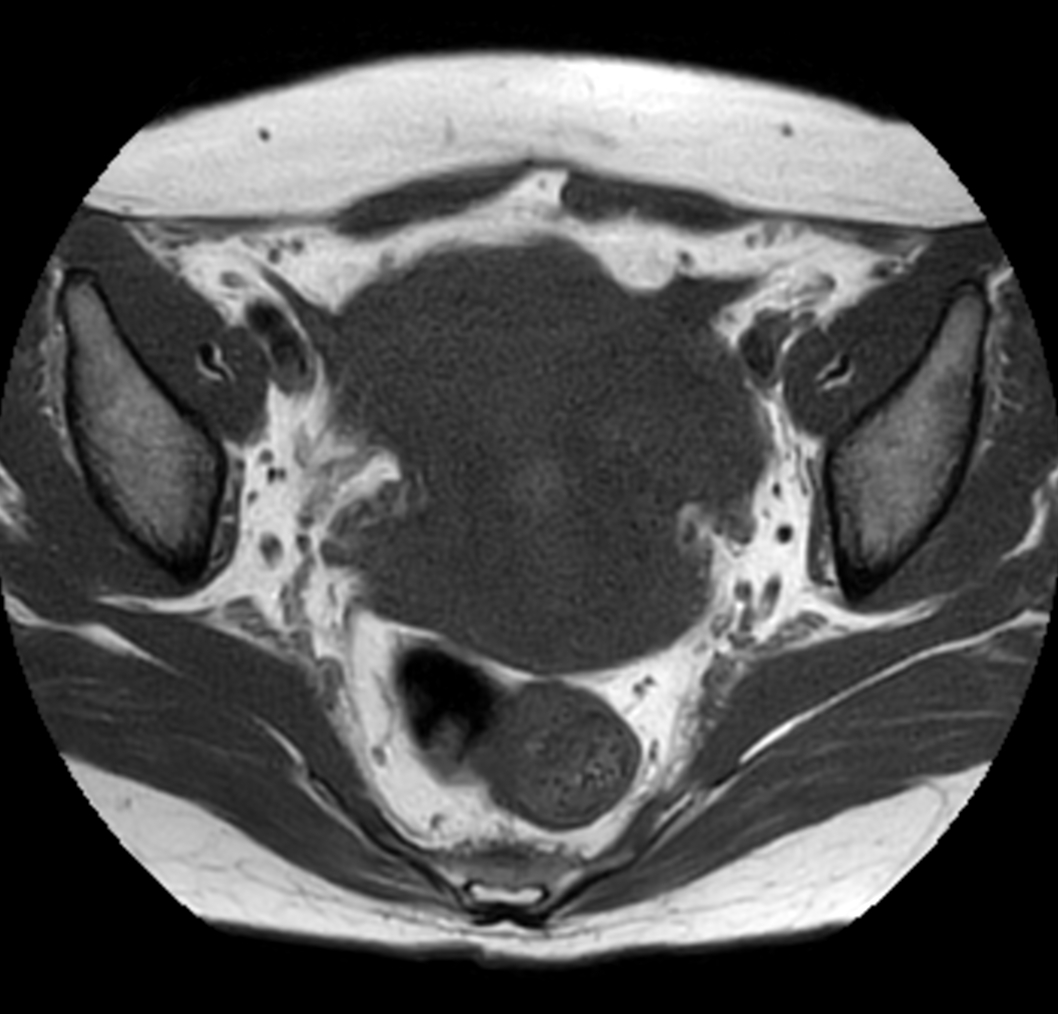

Axial MultiVane XD - T2w TSE